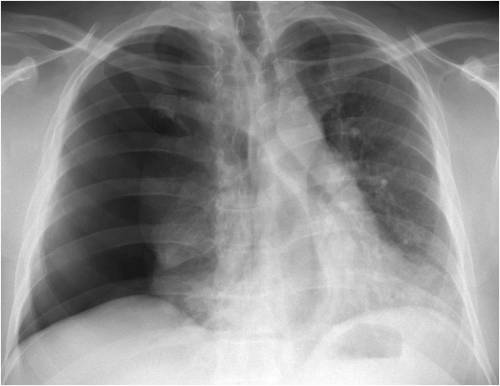

El neumotórax espontáneo es una condición en la cual se acumula aire en el espacio entre la pared torácica y los pulmones, lo que puede provocar la colapsión parcial o total de un pulmón. Cuando se trata de la recurrencia de esta afección, hay varios factores a considerar.

Cuando se produce un neumotórax espontáneo, este espacio se llena de aire, lo que puede deberse a la ruptura de pequeñas bolsas de aire en la superficie del pulmón, llamadas blebs o bullae. Estas bolsas pueden romperse repentinamente, liberando aire en el espacio entre el pulmón y la pared torácica. Como resultado, el pulmón afectado puede colapsar parcial o totalmente, lo que interfiere con la capacidad del paciente para respirar normalmente.

Los síntomas de un neumotórax espontáneo pueden incluir dolor repentino en el pecho, dificultad para respirar, sensación de opresión en el pecho y, en casos más graves, cianosis (coloración azulada de la piel debido a la falta de oxígeno). La gravedad del neumotórax puede variar desde casos leves que no requieren tratamiento hasta situaciones más graves que pueden amenazar la vida y requerir intervención médica urgente.